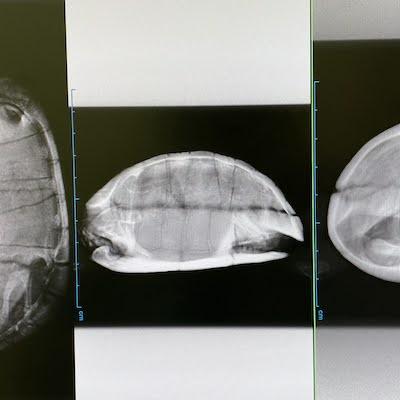

と言いつつ寒そうにしているカメたちの水槽に

まだヒーターを入れてない我が家…(汗)